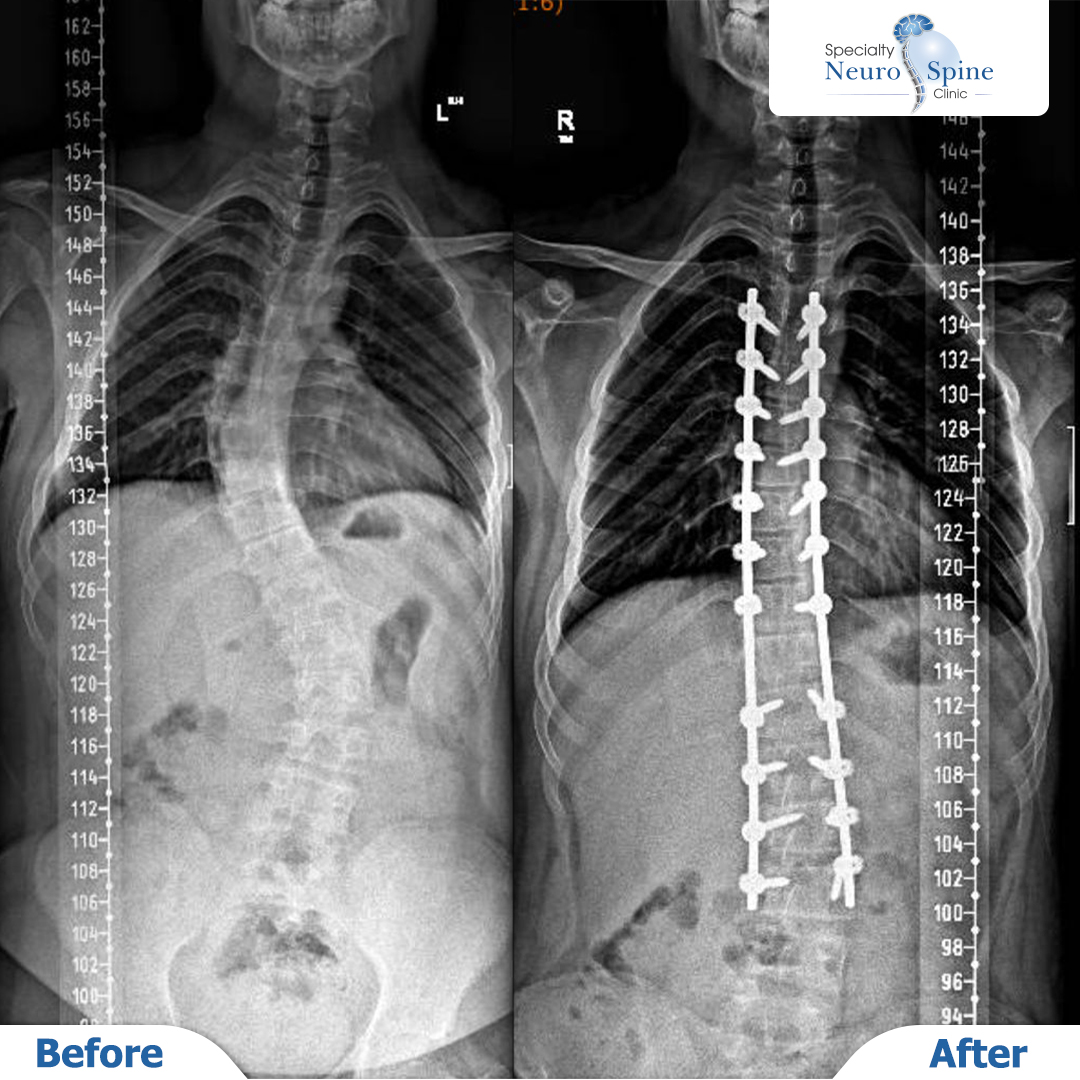

X-ray images of our dear patient, Moataz, 16 years old, from Iraq.

He underwent scoliosis correction surgery covering T4 to L3, utilizing minimally invasive endoscopic techniques. Remarkably, he was able to walk naturally just one day after the procedure.